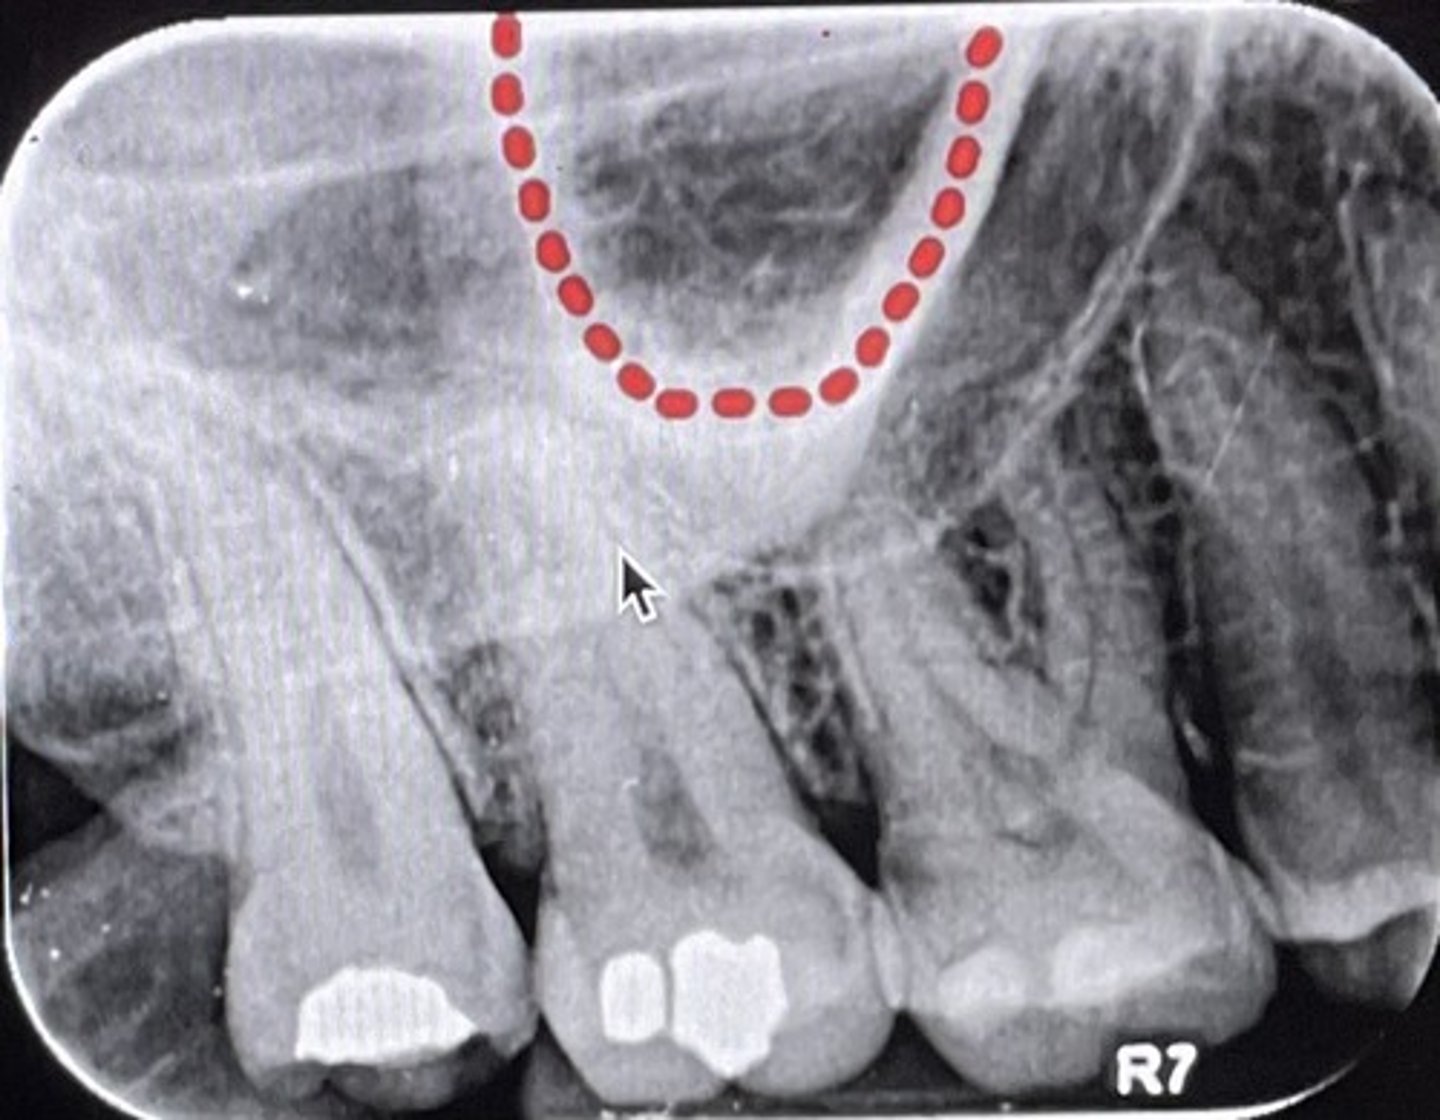

What are the red dots representing?

Dental papilla space